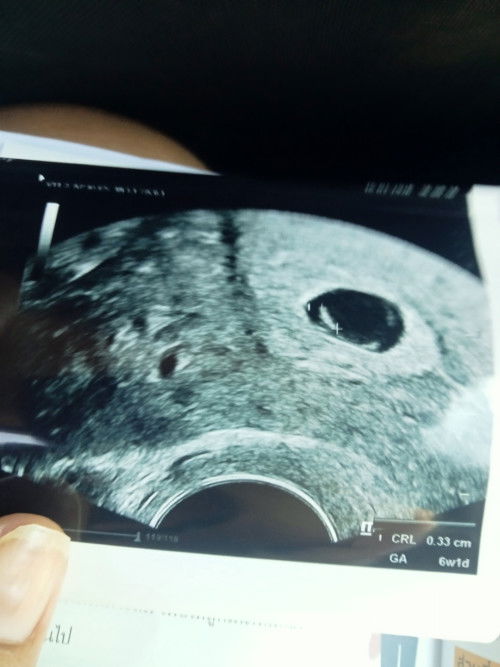

5สัปดาห์ อัลตราซาวด์เจอแต่ถุงครรภ์

ปจด.ขาดได้6วัน ตรวจขึ้น2ขีด วันนี้เลยไปอัลตราซาวด์ดูให้ชัวร์ เจอแต่ถุงครรภ์ ยังไม่เจอน้อง แบบนี้เสี่ยงอะไรไหมคะ ท้องแรกมือใหม่ทั้งแม่ทั้งพ่อ ตอนนี้กังวลมากค่ะ

6+1 สัปดาห์ อัลตร้าซาวด์ผ่านช่องคลอดค่ะ

Post reply image